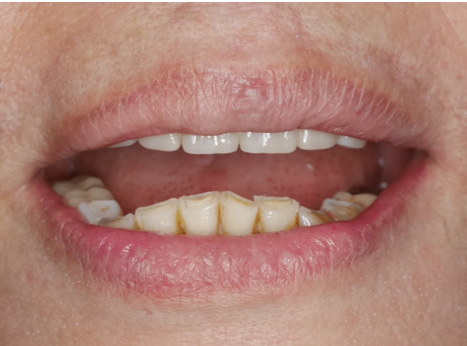

2️⃣ 意外變「順」眼! 除了恢復咀嚼功能,更讓廖阿姨驚喜的是,原本因缺牙和牙橋造成的輕微「凸嘴」外觀,竟然也一併改善了!臉型線條變得更柔和、更自然,笑容也更加自信迷人!😄

從「食不下嚥」到「大快朵頤」,從「不敢笑」到「笑開懷」,廖阿姨用親身經歷告訴我們:牙齒健康,是晚年幸福生活的基石!

林先生對於治療過程的舒適度及快速恢復固定咀嚼功能感到非常滿意。擺脫了活動假牙的束縛,他終於能夠自在、有力地享受各種美食,重拾品嚐的樂趣與生活的自信。從高雄北上的辛苦旅程,換來了一口穩固好用的新牙,林先生的笑容說明了一切。